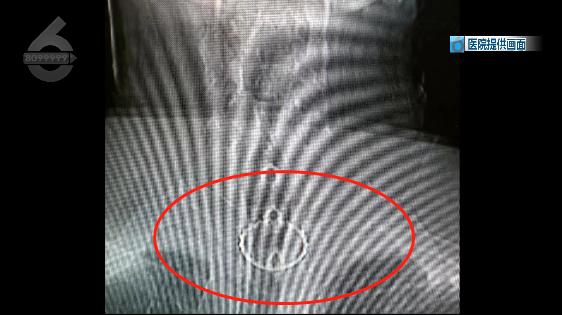

昆明同仁醫(yī)院耳鼻咽喉科 主治醫(yī)師  金麗娟:“體檢的時候照了個胸片,因為啤酒瓶蓋是金屬嘛 ,顯影在片子上就看得出來,有個啤酒瓶蓋就卡在了食道里面!

不看不知道,一看嚇一跳,在影像報告中顯示,李先生的食管上段竟然有一個明顯的圓形異物,疑似為啤酒瓶蓋。